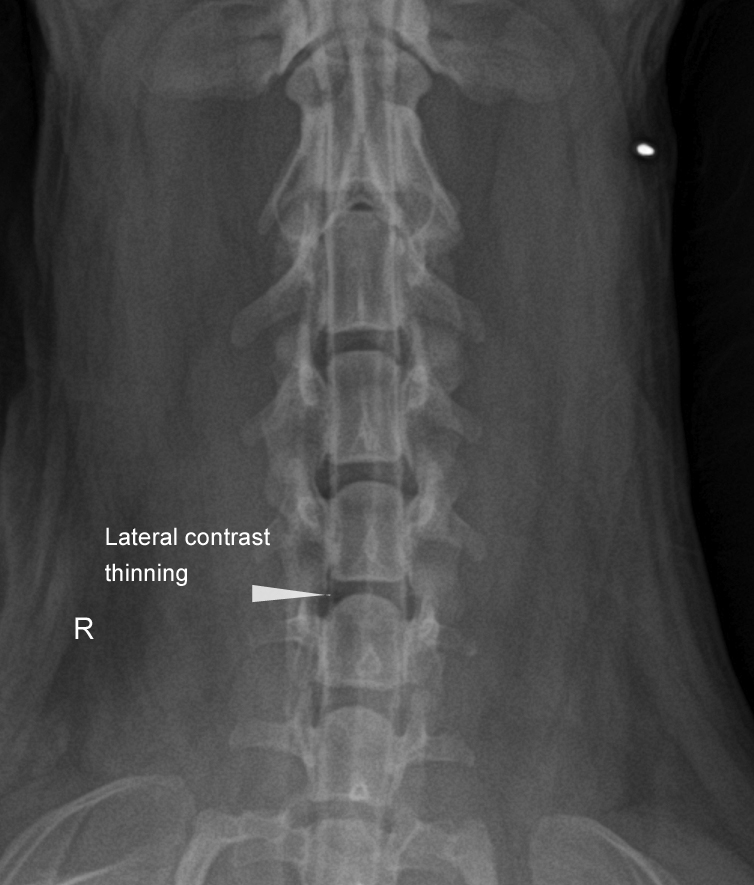

A cysternal myelography was performed, because a cervical compression was suspected.

The lateral myelograms revealed good contrast flow through the cervical area, but a ventral “double column” sign was visible at C5-C6. There was mild widening of the “myelon" at C5-C6 space on the ventrodorsal view and mild contrast thinning on the right.